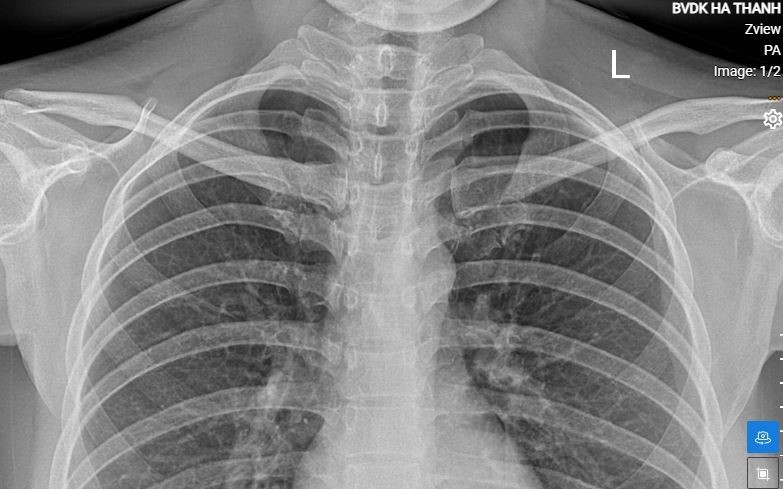

Chẩn đoán thoát vị Bochdalek thường được thực hiện thông qua các phương pháp hình ảnh như siêu âm, X-quang hoặc CT scan. Khi được chẩn đoán, việc điều trị thường bao gồm phẫu thuật để khôi phục lại vị trí của các cơ quan và sửa chữa cơ hoành. Phẫu thuật thường được thực hiện sớm để giảm thiểu nguy cơ mắc các biến chứng nghiêm trọng và cải thiện khả năng sống sót của trẻ. Sau phẫu thuật, trẻ cần được theo dõi sát sao để đảm bảo quá trình hồi phục diễn ra thuận lợi.